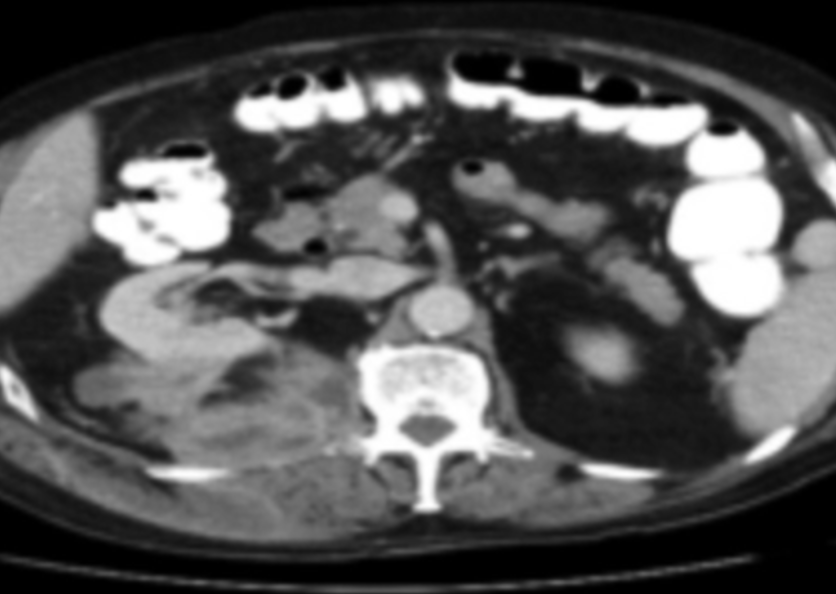

A 74-year-old man presented to his primary care provider with a 1-month history of new-onset low back pain.